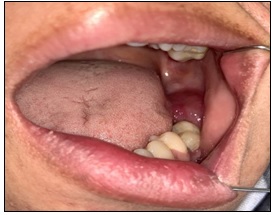

In intraoral examination, a sessile exophytic lesion with a smooth surface measuring 2 x 2.5 cm was observed on the posterior ridge of the left mandibular second molar, which was red in most areas with telangiectasia and normal in some areas. On buccal expansion palpation, bony hard was observed in the area of left mandibular second molar with a high probability of extension to the ramus, which also slightly involved the lingual side. However, the consistency of the ridge surface lesion (the mass resulting from bone perforation) was rubbery. Left mandibular second molar had anterior displacement and grade 1 looseness, but there was no tenderness or neurological symptoms. In examining the contact of the lesion with the tooth, the distolingual cusp of left maxillary tooth 7 and the maxillary ridge were in contact with the lesion, but no ulcer was formed (Figure 1).

Figure 1. Intraoral View: Exophytic lesion without base and smooth surface with red color and telangiectasia in the posterior ridge area of left mandibular second molar.